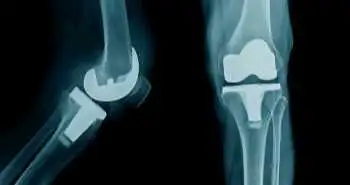

Study demonstrating the augmented wound leakage in total knee arthroplasty with local infiltrative analgesia

This study was done to assess the occurrence of early wound leakage and after surgery pain following knee arthroplasty after the LIA with 30 cc ropivacaine 2% and 1 mg epinephrine.

A recent study illustrated that there was an elevation in the chances of early wound leakage on the introduction of local infiltrative analgesia (LIA) with 1 mg of epinephrine and 30 mL of ropivacaine 2%. LIA after adding up ropivacaine and epinephrine enhances the chances of early wound leakage after knee arthroplasty.

In this study, the prevalence of early wound leakage subsequent to knee arthroplasty after the alteration of local infiltrative analgesia with 1 mg epinephrine and 30 cc ropivacaine 2% was evaluated. Five hundred two patients who were undergoing a knee arthroplasty participated in this study. One group received local infiltrative analgesia with the addition of 120 mL 2 mg/mL ropivacaine(ROPI- group).  The second group received LIA by adding up 150 mL 2 mg/mL ropivacaine with 1 mg epinephrine (ROPI + group). The primary effect noted was early wound leakage. The 10-point numeric rating scale (NRS) was also assessed, and the data was assessed with the use of logistic regression.

The prevalence of wound leakage was more in the ROPI + group as compared to ROPI- group. The postoperative pain assessment was the same for ROPI + and ROPI- group.

It was concluded that alteration of the LIA with epinephrine and ropivacaine resulted in augmented cases of early wound leakage in knee arthroplasty.